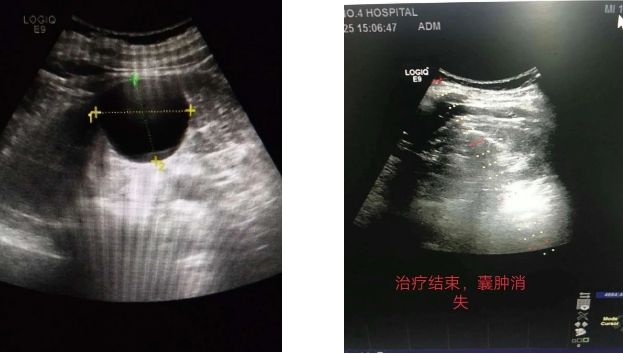

肾囊肿虽是一种常见的良性疾病,但如果囊肿体积较大,则会引起腰部酸胀、不适、疼痛,甚至受外力挤压时,容易造成破裂,出血不止的情况。5月26日,一位60岁的男性丙肝史患者入住淄博市第四人民医院,在正常体检时发现左肾囊肿,囊肿大小5.3×5.2cm。考虑到患者的具体病情,彩超室为其实施了创伤小、疗效好的超声引导下无水酒精硬化治疗。彩超室主任邵宏增和主治医师高珊珊密切配合,精准定位,精确引导,抽得清亮囊液60ml,并注入无水酒精硬化,术后复查超声囊肿消失,患者无明显不适症状,在门诊观察30分钟后,自行走回病房,轻松解决了患者的病痛。

肾囊肿如果小于5cm,又向外突出,不压迫肾脏,一般不需要治疗。如果囊肿较大,压迫肾脏血管或肾盂,影响血流或排尿功能时,应该进行穿刺减压治疗。用超声诊断肾囊肿方便易行,图像清晰,故在超声引导下经皮穿刺肾囊肿无水乙醇硬化治疗得以实现。